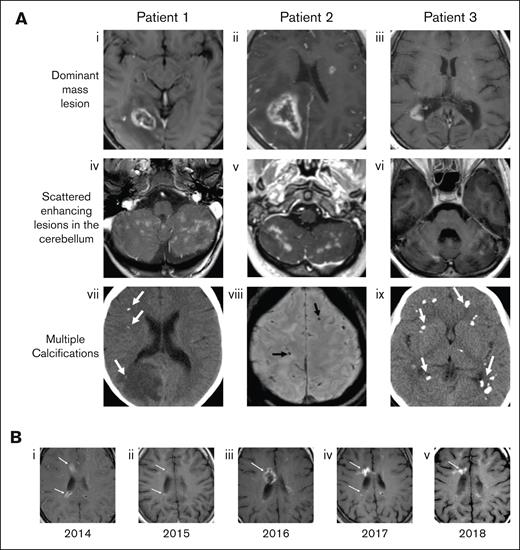

MRI was performed in all patients at the time of presentation. Defining features of the radiographic appearance are shown in Figure 2 and include a dominant, ring-enhancing lesion together with small, scattered enhancing foci, and calcifications throughout the cerebellum. The parietal lobe was the most frequent location of the dominant lesion. Significant vasogenic edema with accompanying midline shift as well as areas of diffusion restriction were common. Four patients also had enhancing lesions in the spinal cord. Repeat imaging throughout the clinical course of each patient demonstrated the waxing and waning nature of the lesions, with increases and decreases in enhancement over time. Patients demonstrated declining neurological function, both motor and cognitive, over a period of years.

Characteristic radiographic findings of FANS and their evolution over time. (A) Representative MRI findings shown for 3 patients with FA in our cohort. (Ai-iii) Axial postcontrast T1-weighted MRIs show focal ring-enhancing mass lesions. (Aiv-vi) Contrast-enhanced images through the cerebellum show multiple enhancing lesions. (Avii,ix) Noncontrast computed tomography and (Aviii) susceptibility weighted MR images demonstrate multiple calcifications in each case (arrows). (B) Axial T1-weighted MR images from patient 3 over a 5-year span, demonstrating the waxing and waning of lesions. (Bi) In 2014, enhancing lesions are seen on the anterior and posterior margin of the right lateral ventricle (arrows), both of which markedly regress a year later (Bii, arrows). (Biii) In 2016, the anterior lesion recrudesces (arrow), then decreases again over the next 2 years, with some waxing and waning of the posterior lesion (Biv-v, arrows).